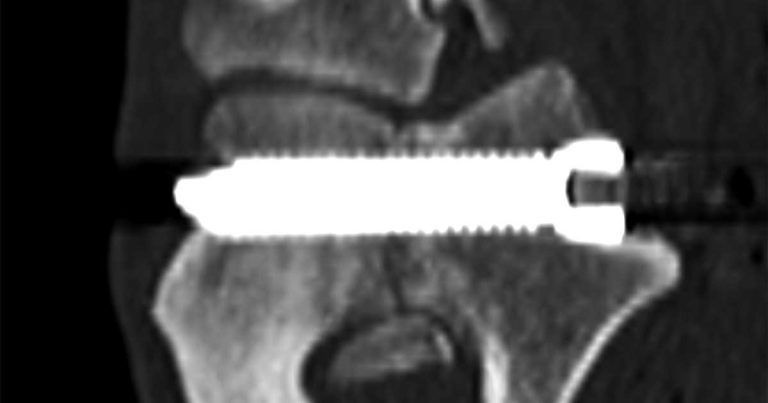

A postoperative CT confirmed an excellent trajectory of the screw, with the very tip of it protruding laterally (Figure 6).